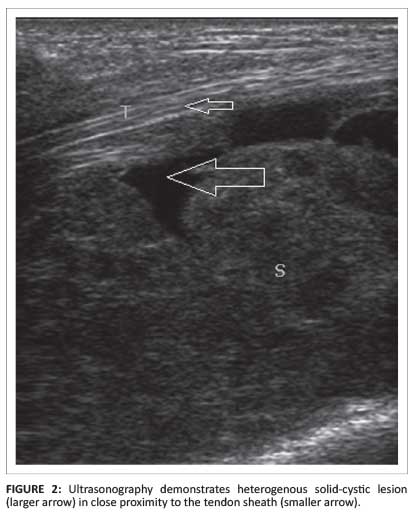

On chest radiography, no obvious abnormality was noted. The Mantoux test was positive (induration of 15 mm). Nerve conduction studies (NCS) revealed features suggestive of median nerve compression; there was increased distal motor latency (5.1 milliseconds) and distal sensory latency (4.2 milliseconds) of the median nerve with decreased median nerve conduction velocity (41 m/s). Radiography of the hand and wrist revealed diffuse soft-tissue swelling without any osseous abnormality. US of the wrist revealed a heterogeneously hypoechoic bilobed mass (Figure 2) containing both solid and cystic components in and around the flexor tendon sheaths, with involvement both above and below the flexor retinaculum.

Radiological modalities play a pivotal role in the diagnosis of compound palmar ganglion. Plain radiography may demonstrate soft-tissue opacity and evidence of bone destruction. Computed tomography (CT) can show bone destruction and simultaneously demonstrate the solid-cystic nature of the lesion. B-mode US is a very useful tool to visualise, in real time, the proximal and distal extent of the lesion, and its contents and relation to the flexor tendon sheath. Usually, heterogenous solid-cystic components are noted in and around the flexor pollicis longus, flexor digitorum superficialis and flexor digitorum profundus tendons, both proximal and distal to the flexor retinaculum. MRI, by virtue of its excellent soft-tissue delineation, is the best imaging modality in this context. Pre- and postcontrast T1, T2 and 3DFGRE sequences in both the axial and coronal planes are commonly used. As the lesion is predominantly fluid-containing with thickened synovium and tenosynovium, it is hypointense on T1W1; on T2WI, the fluid component is hyperintense and the thickened synovium and tenosynovium appear hypointense. T2*-weighted images also reveal the fluid component to be hyperintense and the solid component to be hypointense.3, 4On postcontrast studies, there is usually rim enhancement of the lesion.